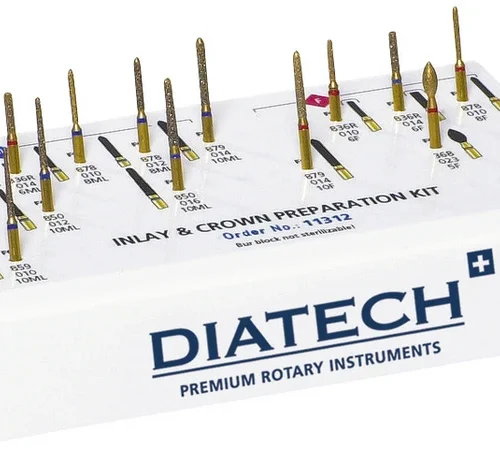

- Normal kornstørrelse (80-120 µ)

- svart = ekstra grov (180 µ)

- grønn = grov (120-135 µ)

- rød = fin (45 µ)

- gul = ekstra fin (35 µ)

- hvit = ultra fin (5-15 µ)

- oransje = UU-fin (2-4 µ)

- Kroner og broer – fullfasadekroner, helkeramiske kroner, helkeramiske inlays og onlays, metall-keramiske kroner, tannrestaureringer – komposittrestaureringer

- Maks. turtall (ISO 005-014) 450.000 o/min., turtall (ISO 016-023) 300.000 o/min., turtall (ISO 025-045) 120.000 o/min.